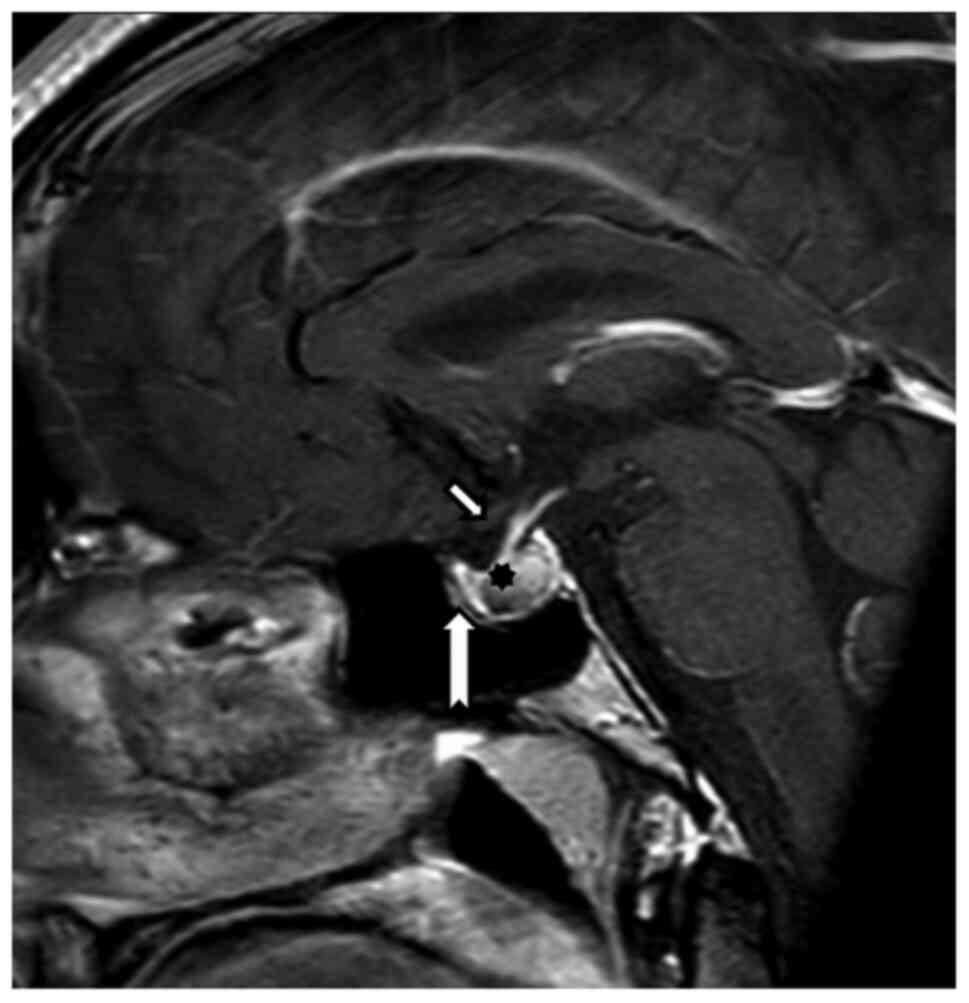

Because of the reduced visual acuity, MRI examination was recommended, which revealed (August 2019) expansion of the Turkish saddle with hemorrhage, with probable benign etiology. The pituitary gland itself was pushed away ventrally (Fig. 1).

Figure 1

Magnetic resonance imaging, T1 postcontrast sequence, sagittal plane. Examination 5/8/2019. Non-homogeneous hypophysis expansion matched the most suspicious bleeding. There was no contact with the optic chiasm. Ventral and cranial infundibulum dislocation was evident. Short arrow indicates chiasm, long arrow indicates tuberculum sellae and asterisk indicates hypophysis.

Magnetic resonance imaging from 12/2020 showed a regression of pituitary expansion. There was a clearly defined distance of the chiasm and cranial contour of the pituitary gland and a common location of the infundibulum (Fig. 2).

Figure 2

Control magnetic resonance imaging at a time when the first perimetric changes had appeared. T1 postcontrast sequence, sagittal plane. Regression of the hypophyseal expansion. A clearly defined distance between the chiasm and the cranial hypophyseal contour, with a regular infundibulum position. Short arrow indicates chiasm, long arrow indicates tuberculum sellae and asterisk indicates hypophysis.